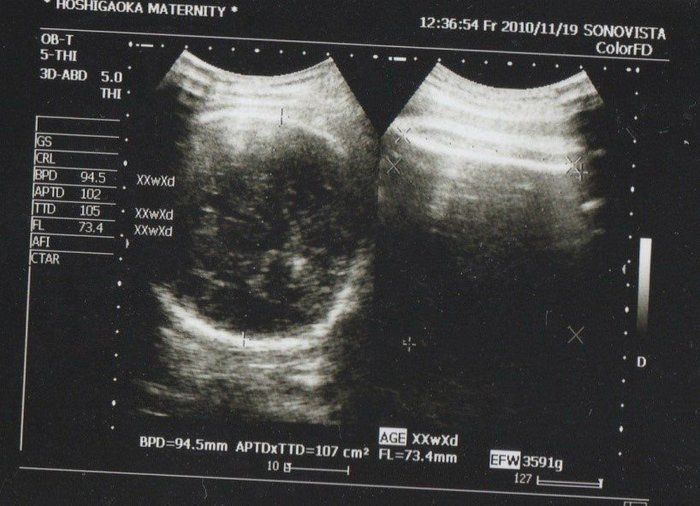

クリコさんの妊娠37週目のエコー写真

推定体重3000gにまで増えていてビックリ。私自身が2600gで生まれており、「お産は母親に似る」と聞いていたので、勝手に少し小さめで生まれてくると思っていました。「4000g超えになるかも」と不安を覚えました。私は既に10kg近く増加になっていたので、この時期から意識的に散歩と、食べすぎに気をつけ、臨月は赤ちゃんの増加分(約1kg)にとどめ、最終的に10.5kg増で抑えました。